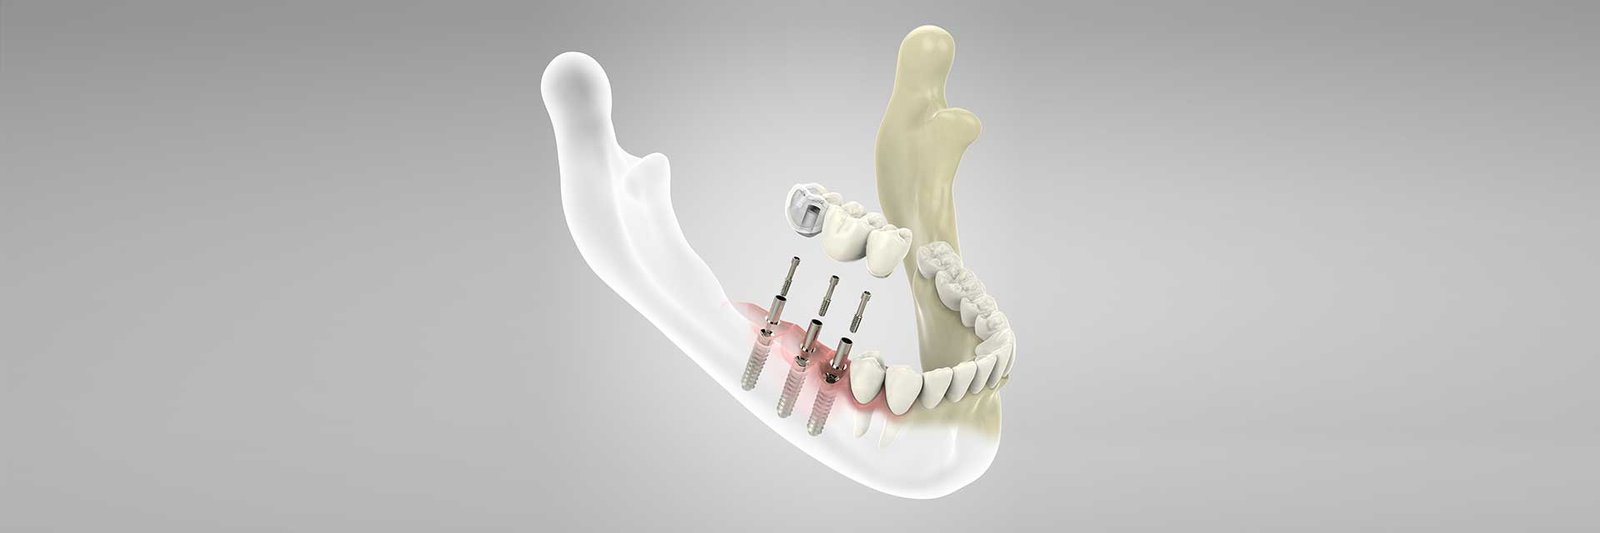

Τα εμφυτεύματα είναι τεχνητές ρίζες τιτανίου ή κεραμικές. Είναι η ιδανική λύση,για να αποκαταστήσουμε χαμένα δόντια.

3D ανάλυση οστού.

3d ανάλυση